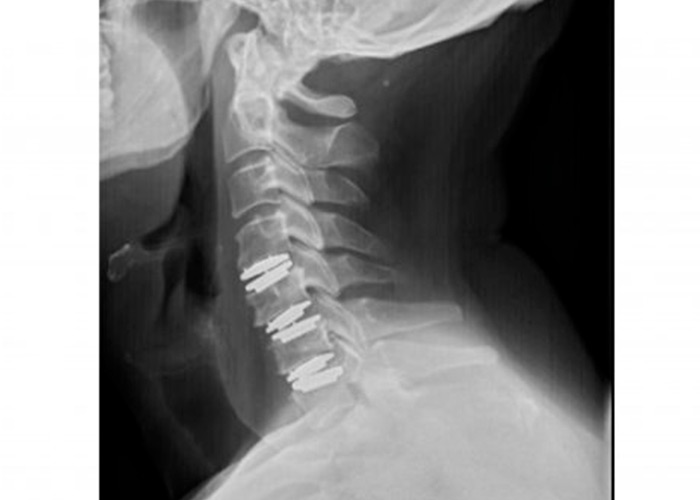

protesis-cervical-movil-instituto-cac

Postoperatorio

En menos de 5 horas el paciente se recupera de la operación. Asimismo, la movilización del cuello comienza desde el primer momento y no se precisa collarín ni otros inmovilizadores.

Por último, el paciente recibe el alta hospitalaria al día siguiente de la operación.